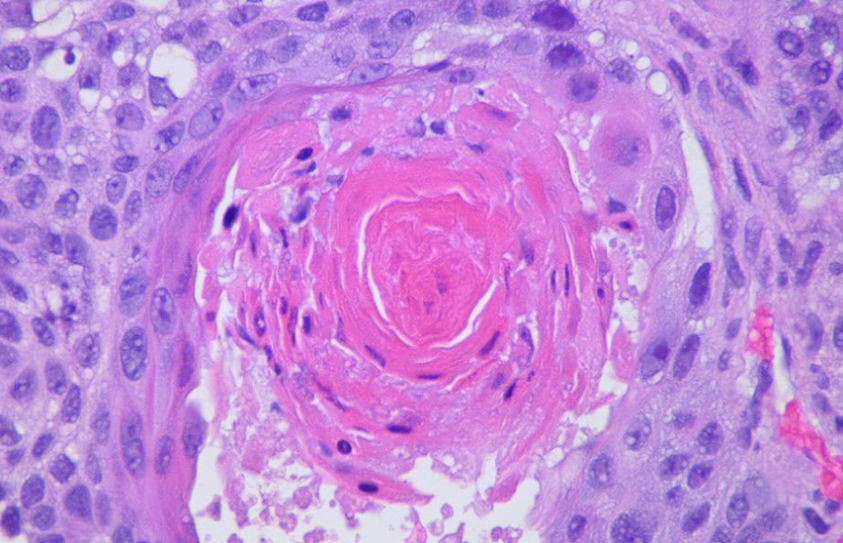

Google's Algorithms Are Already Outperforming Pathologists

One of the more difficult things a doctor can do is diagnose cancer. That's not just because of the life-changing effects such a finding can have, but because distinguishing a...